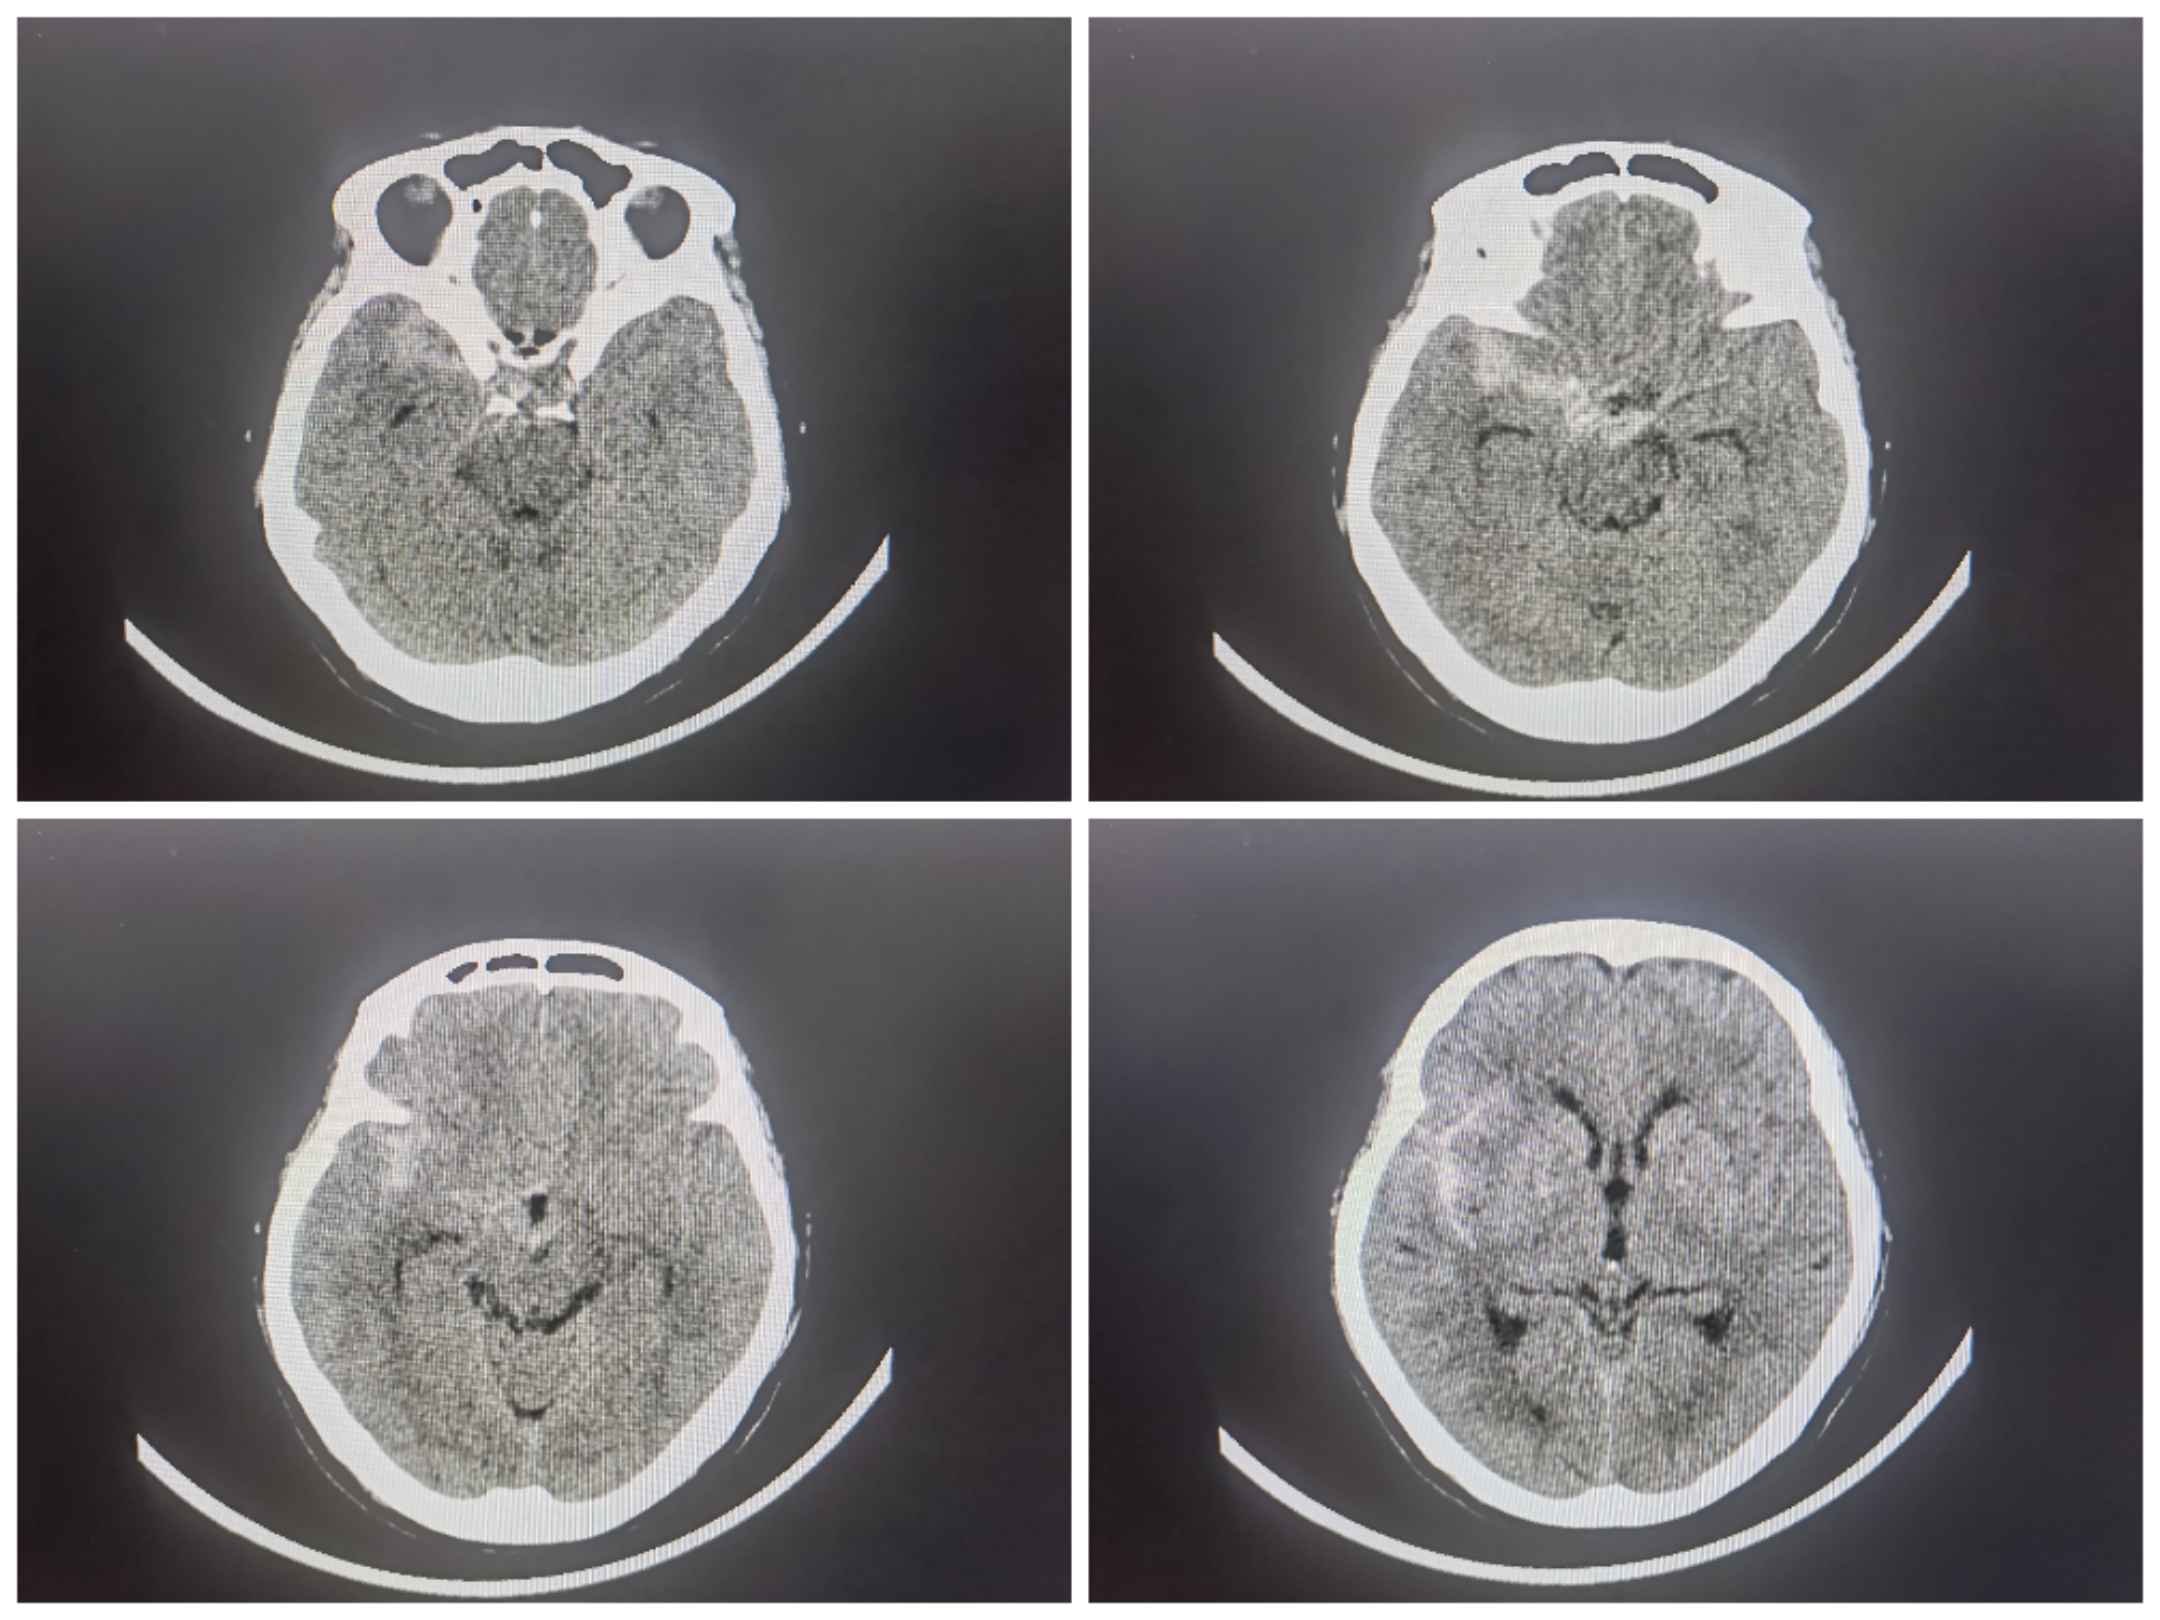

SAH入院,Hunt-Hess分级2级,

CTA提示不规则分叉部、多分叶、动脉瘤,瘤颈波及上干为主